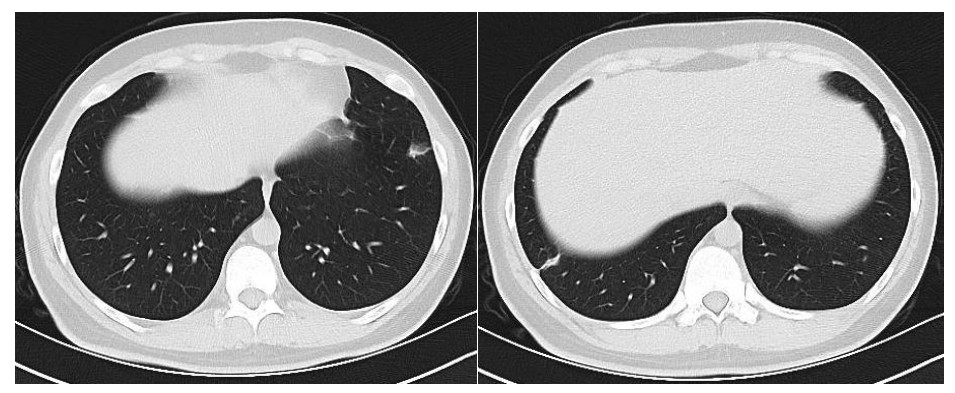

患者男性,21岁,主因“间断发热、寒战伴头晕头痛2周”于2021年11月18日急诊收入院。患者诉2周前进食烧烤后出现发热,体温最高可达42℃, 伴畏寒、寒战、咽痛、头晕、头痛、乏力,就诊于本院耳鼻喉科后,查体见扁桃体有脓点,快测降钙素原(procalcitonin,PCT)为37.27 ng/mL,胸部CT检查未见异常,考虑诊断为“急性化脓性扁桃体炎”,先后给予左氧氟沙星、阿奇霉素抗感染及甲泼尼龙控制炎症后上述症状未见明显好转,为进一步治疗,收入急诊病房治疗,既往体健,入院时查体:体温41℃,脉搏98次/min,呼吸频率23次/min,血压120/60 mmHg(1 mmHg=0.133 kPa),患者神志清楚,急性病容,精神较差,颈部浅表淋巴结触及肿大,右侧较大约2.0 cm ×0.5 cm,左侧较大约1.3 cm×0.7 cm,质软,活动度好,界限清楚,有压痛,表面皮肤无红肿,无破溃,双肺呼吸音清,未闻及干湿性啰音,心脏听诊无杂音,腹软,无压痛及反跳痛,双下肢无水肿。血常规检查白细胞计数10.49×109/L, 中性粒细胞百分比94.6%,血红蛋白120 g/L, 血小板计数107×109/L,PCT 42.83 ng/mL,白介素6(interleukin, IL-6)980.30 pg/mL,C反应蛋白211 mg/L,G试验、GM试验阴性。胸部CT检查示右肺上叶可见一单发实变影,其内可见空洞(图 1)。根据病史、查体和辅助检查考虑诊断为肺脓肿,给予注射用哌拉西林钠他唑巴坦4.5 g Q8h治疗,入院第2天,患者仍有发热,体温最高38.7℃,给予对症处理,入院第3天患者体温峰值有所下降,体温维持在37~38℃,考虑抗炎有效,痰培养结果回报为纹带棒杆菌,草绿色链球菌(奈瑟菌属),考虑这2种细菌为皮肤或口腔的正常菌群,为条件致病菌,该细菌导致发热的可能性较小,继续给予哌拉西林钠他唑巴坦治疗。入院第5天血培养回报血液中找到坏死梭杆菌,考虑为血流感染。加用甲硝唑1 g每8 h一次抗感染治疗,复查血常规白细胞计数8.14×109/L, 中性粒细胞百分比81.5%,血红蛋白120 g/L, 血小板计数246×109/L,PCT 3.43 ng/mL,IL-6 13.04 pg/mL,C反应蛋白5 mg/L,炎性指标较前明显下降,考虑抗炎治疗有效,继续目前抗生素治疗。入院第10天患者体温仍有低热,体温36.5~37.5 ℃,复查胸部CT见双肺多发小结节,双肺多发空洞病变,考虑炎性可能(图 2)。颈静脉超声检查提示患者左侧颈内静脉血栓形成,给予依诺肝素0.4 mL每12 h一次抗凝治疗,根据血培养结果、胸部CT表现和颈静脉超声结果,考虑该患者诊断为坏死梭杆菌导致Lemierre综合征(Lemierre syndrome, LS)。用哌拉西林钠他唑巴坦联合甲硝唑治疗后仍有低热,化验检查PCT为0.30 ng/mL,IL-6为3.52 pg/mL,C反应蛋白为3 mg/L,胸部CT示肺部空洞较前增加,考虑感染未完全控制,改为调整抗生素为比阿培南0.6 g每12 h一次联合甲硝唑1g每8 h一次抗感染治疗,治疗1周后患者体温恢复正常,CT检查示双肺多发空洞消失,残留少量索条影(图 3),患者病情好转出院,出院带药给予口服甲硝唑联合阿莫西林抗感染治疗,利伐沙班抗凝治疗,随诊2周后复查胸部CT正常。

右肺上叶可见一单发实变影,其内可见空洞 图 1 入院时胸部CT

LS的致病菌主要为坏死梭杆菌,因此LS也被称为坏死梭杆菌病,其他致病菌包括核杆菌、类杆菌、链球菌和葡萄球菌等[5]。坏死梭杆菌为厌氧革兰阴性多形态杆菌,广泛存在于人类和动物的口腔、上呼吸道、胃肠道和泌尿生殖道的正常菌群。坏死梭杆菌可以产生白细胞毒素、内毒素、溶血素和血细胞凝集素等,白细胞毒素和溶血素与脓肿形成相关,血细胞血凝素可引起动静脉血栓形成,可导致转移性脓肿,弥漫性血管内凝血和血小板减少也与此有关[6]。患者起初为咽部感染,然后通过咽旁间隙侵袭至颈内静脉,形成颈内静脉血栓,脓毒性栓子随着血流播散至肺部,引起肺部脓肿和肺栓塞。本例患者刚发热时胸部CT正常,门诊给予喹诺酮类药物和大环内酯类药物治疗2周后,入院时胸部CT示患者右肺中叶单发实变影,其内可见空洞样变,后随病情发展,胸部CT示双肺多发肺空洞样变,符合LS的临床表现。LS最初表现为喉咙痛或颈部疼痛, 但可出现多种非特异性症状, 如全身僵硬、寒战、发热、颈部淋巴结肿大、眼眶疼痛、骨/关节疼痛、四肢无力、恶心、呕吐等胃肠道症状。最初感染1周后,可以在血液中找到细菌,然后在颈静脉内脓毒性血栓形成,可以肺内形成肺脓肿和脓胸,也可以累及关节[7]